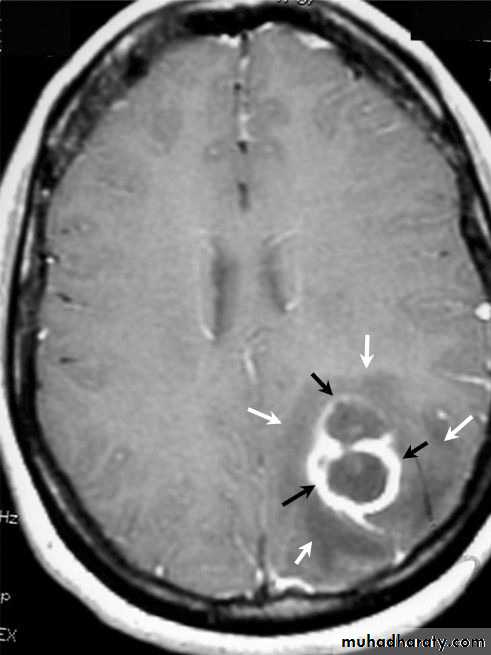

Brain Abscess MRI

د.عبدالرحمن

• B. Radiological Investigations:

• CT or MRI is the investigation of choice.

• CT Brain is performed with and without contrast.

• MRI is done with gadolinium enhancement.

• They will show a single (or multiple) space occupying lesion that is well delineated with an enhancing wall, with variable surrounding oedema.